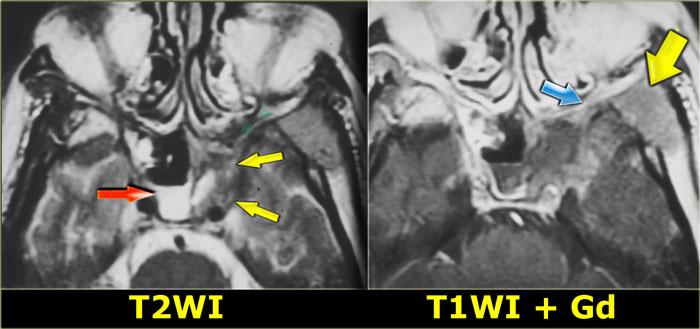

Chuỗi xung T2W mặt phẳng coronal cho thấy sự giãn rộng của mỏm yên.

Chuỗi xung T1W cho thấy mất tín hiệu mỡ bình thường so với bên phải, và lan rộng vào đỉnh hốc mắt (mũi tên đỏ).

Đây là nang nhầy của mỏm yên trước với tổn thương thứ phát dây thần kinh thị giác.